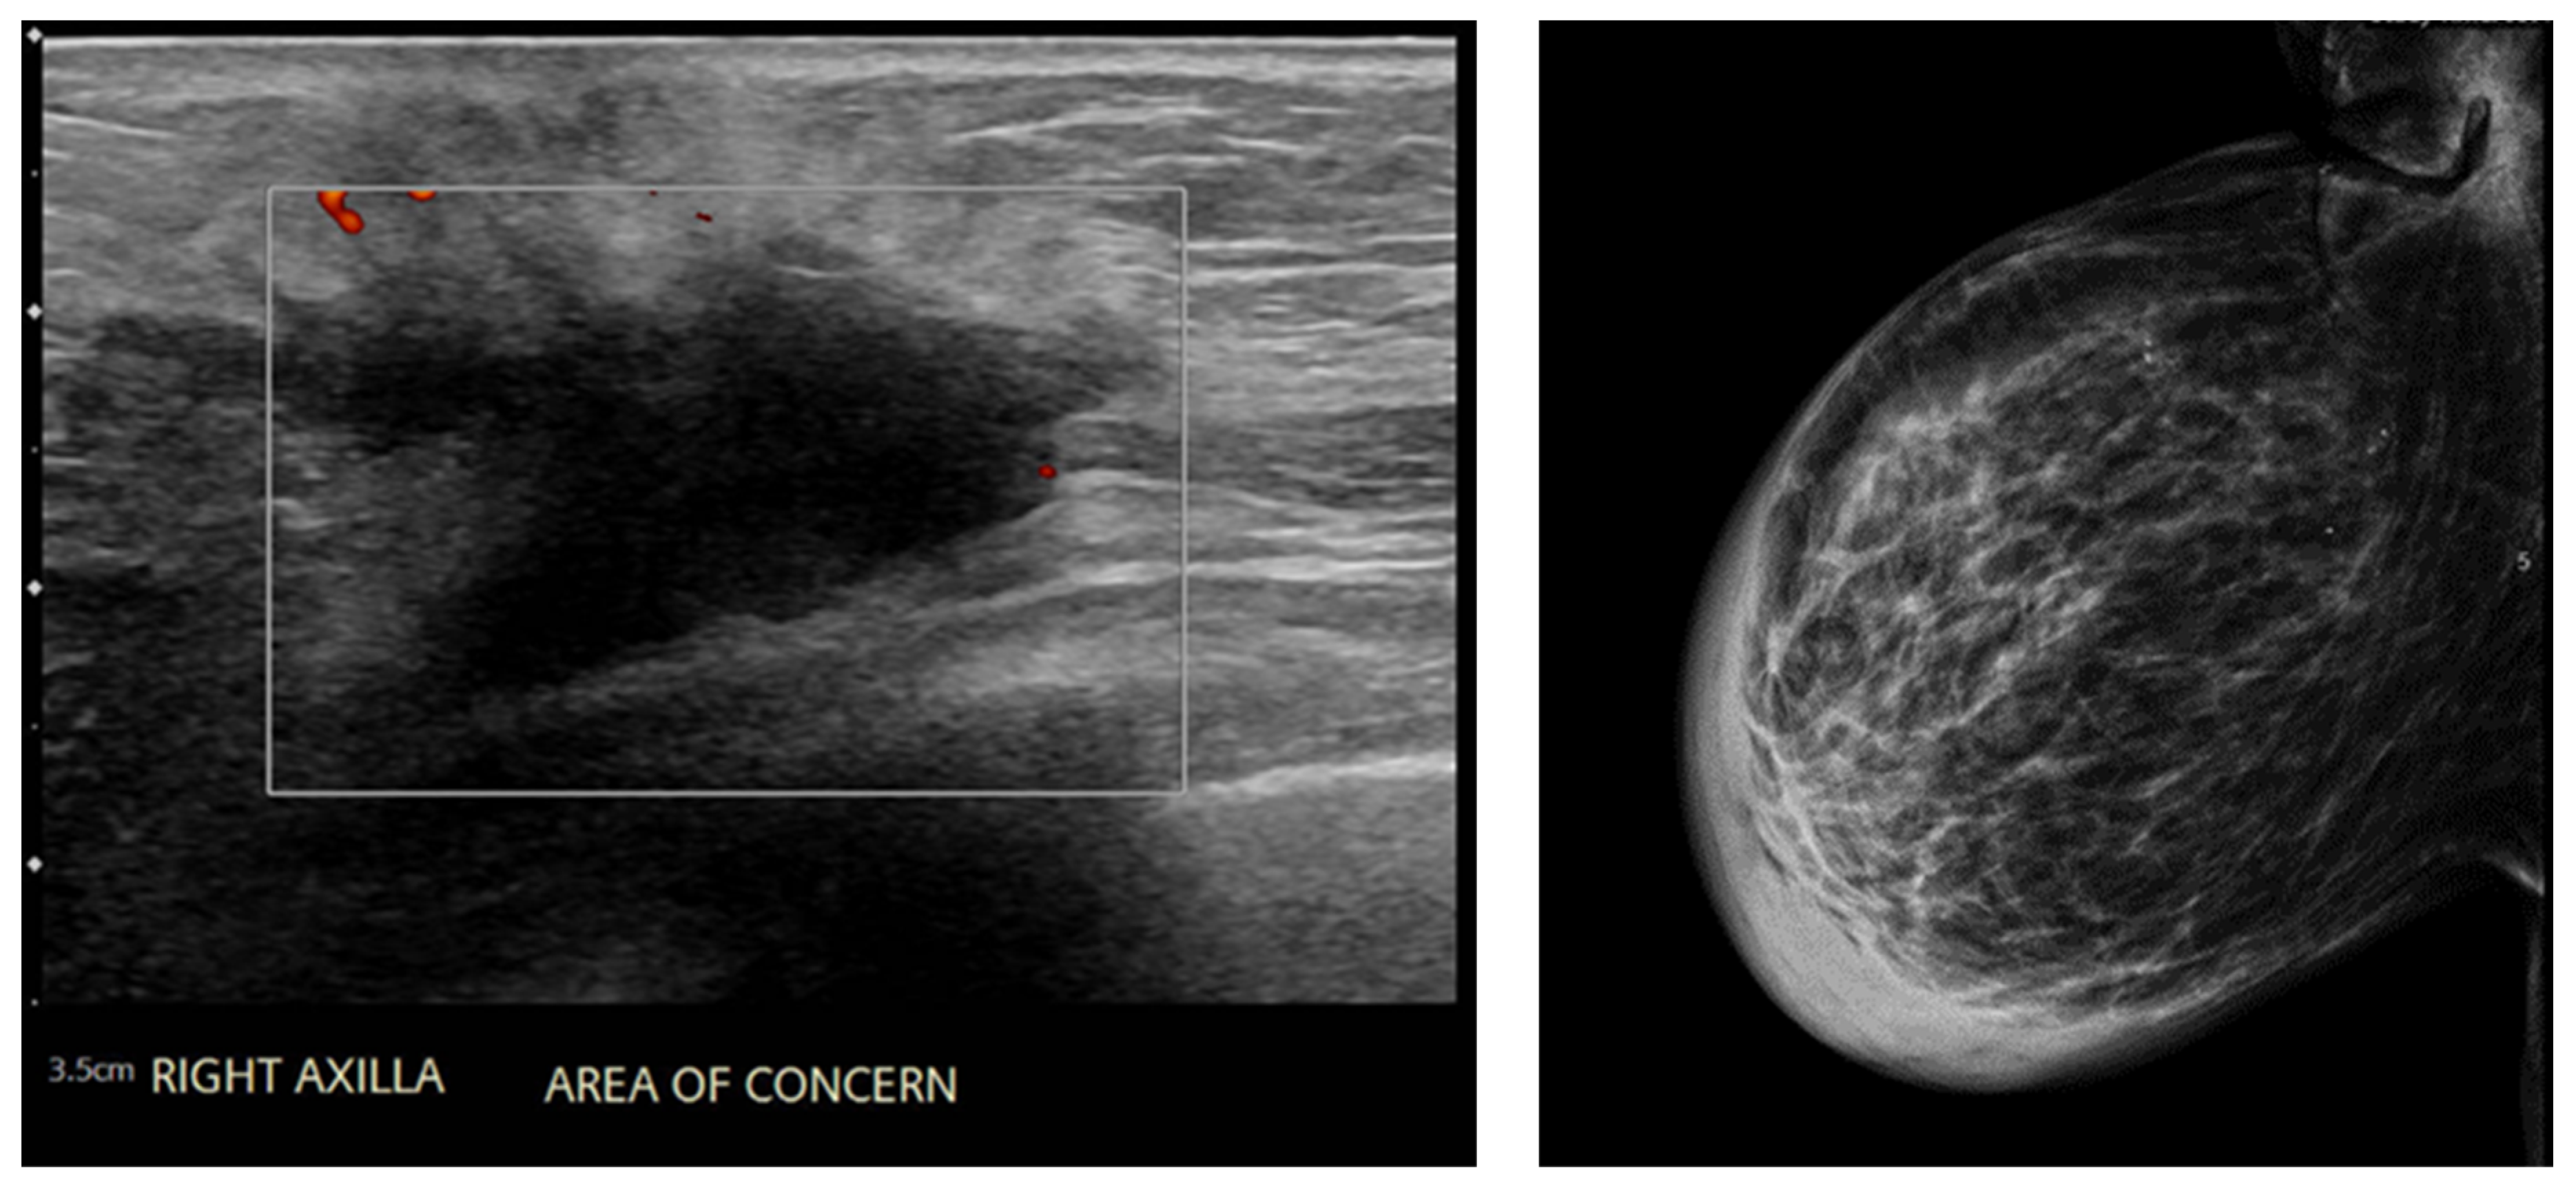

2. Case Presentation